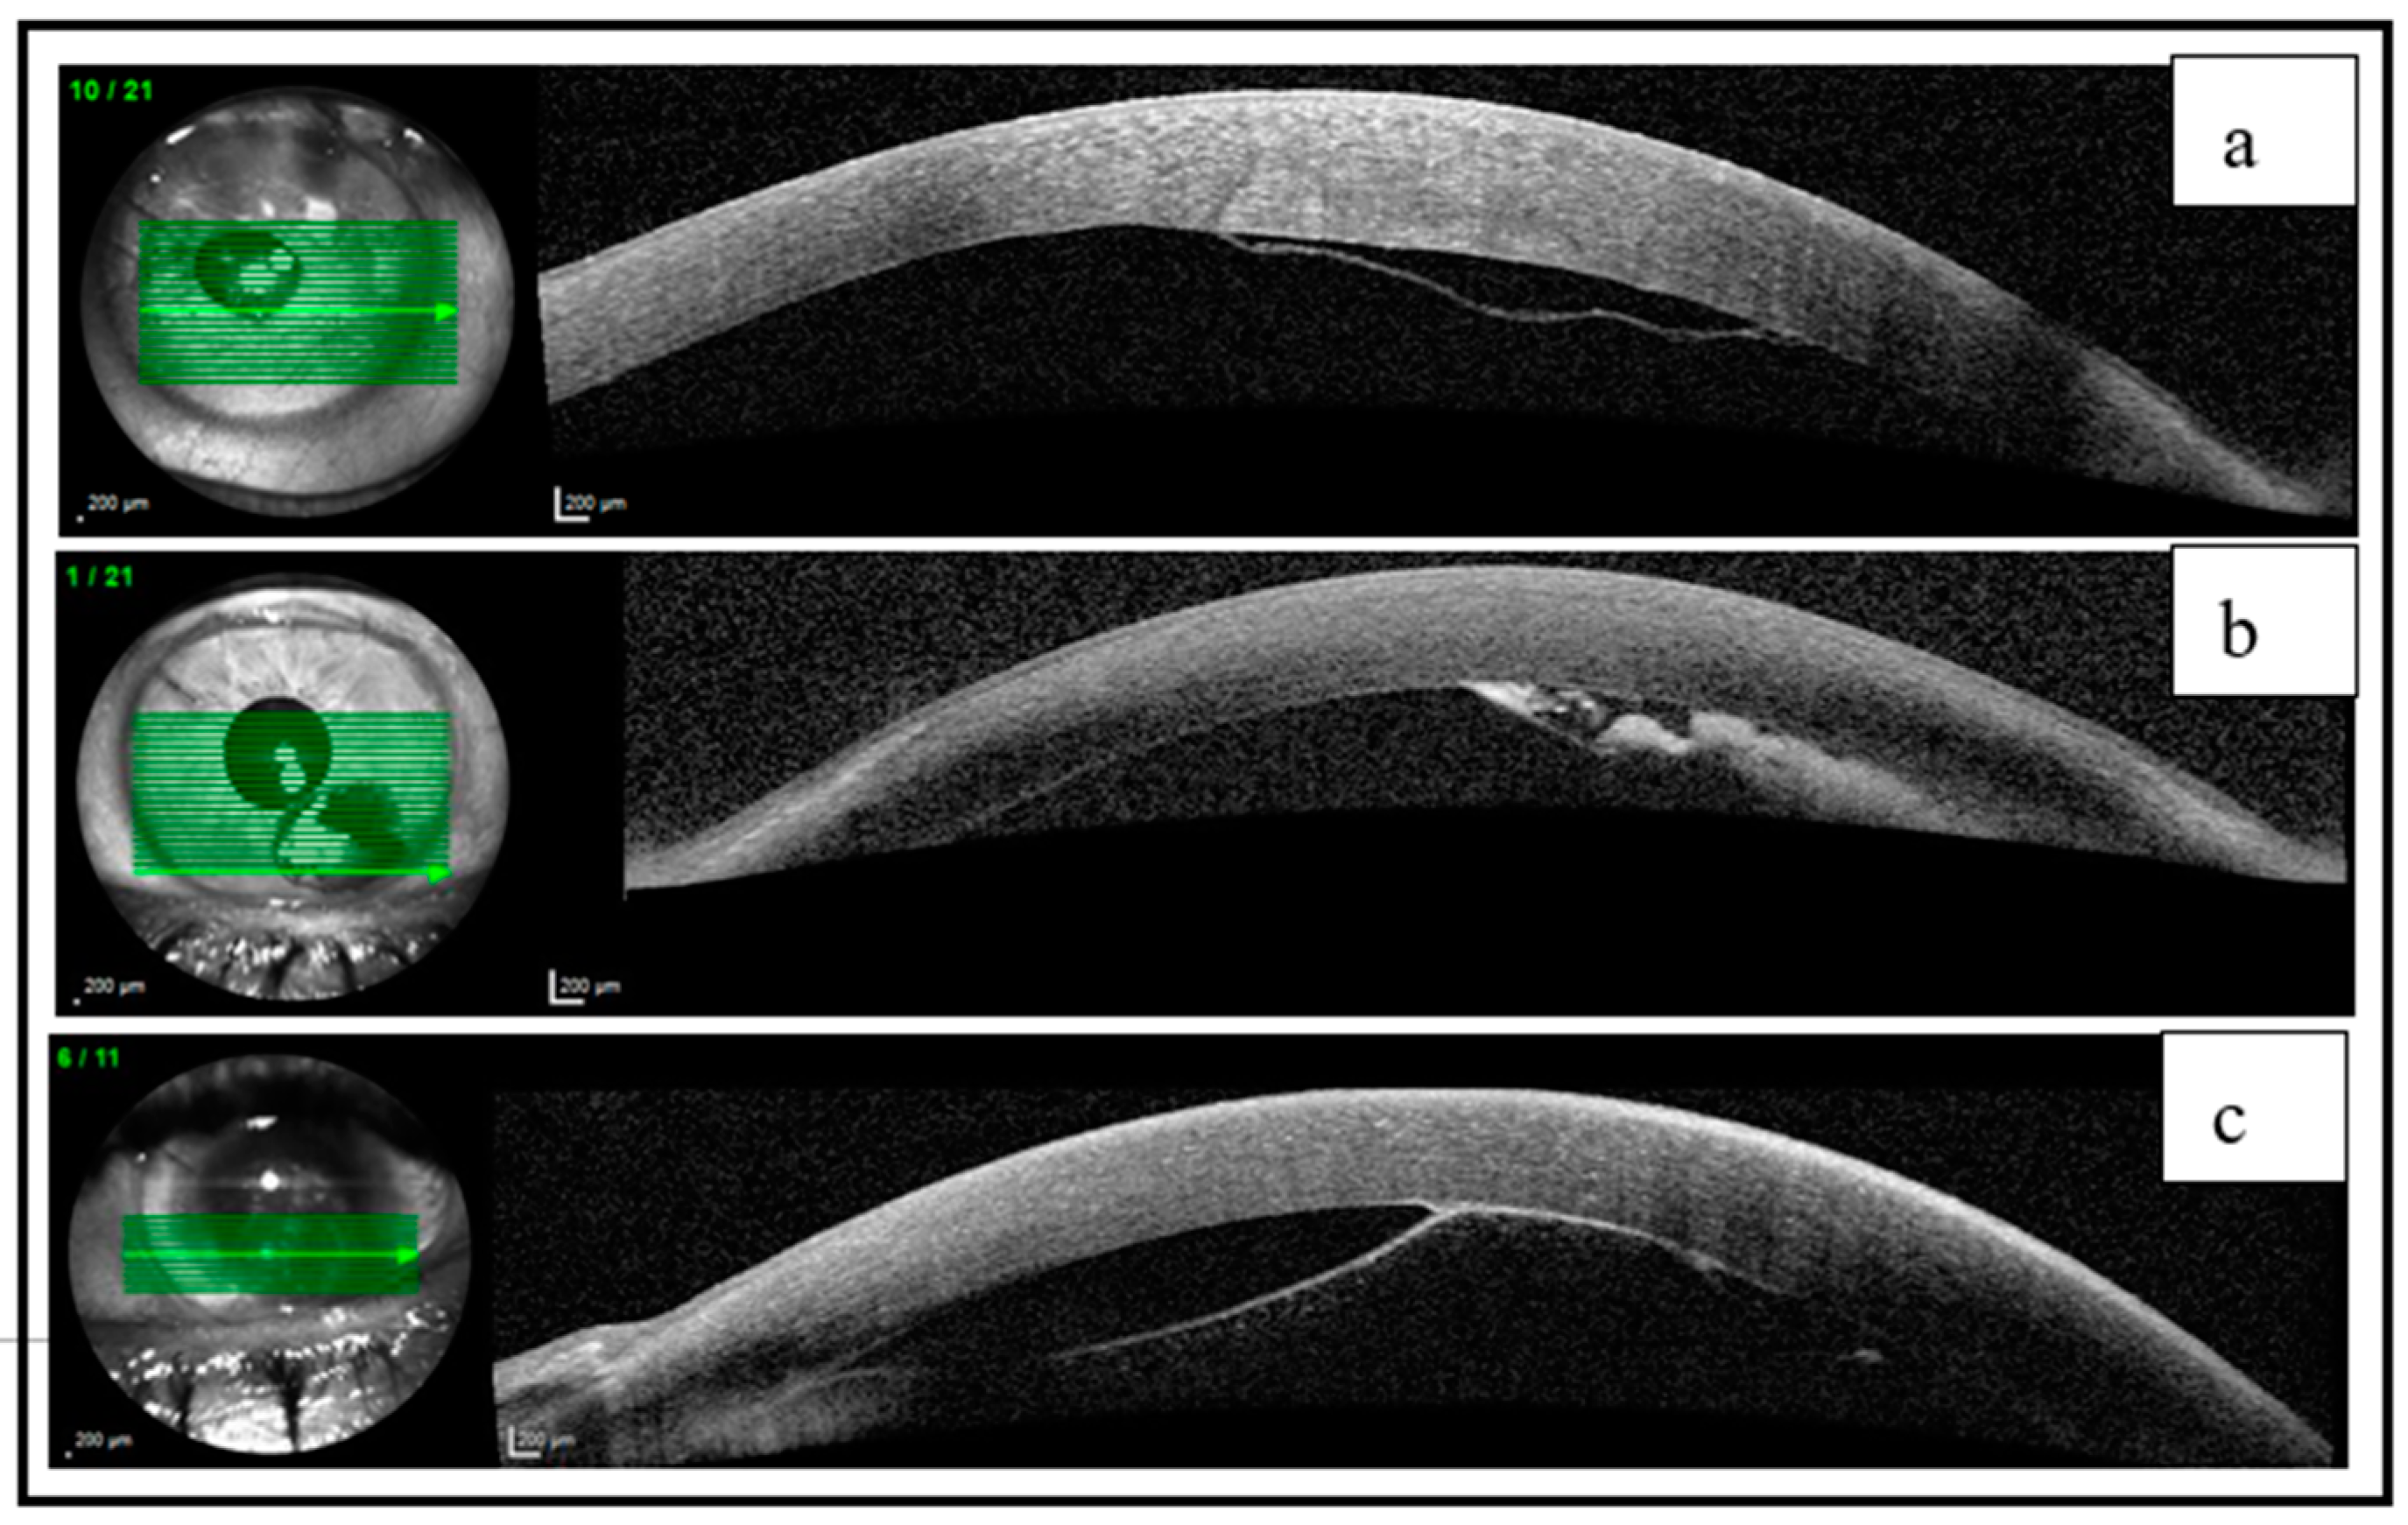

| 1 | 0.3 | Phacocanaloplasty | Non-HDMD | Infero-nasal and infero-temporal | 0.5 | Postoperative drainage | 0.9 | Clear |

| 2 | 0.4 | Phacocanaloplasty | HDMD | Infero-temporal | 0.7 | Observation | 1 | Remnants of HDMD |

| 3 | 0.6 | Phacocanaloplasty | Non-HDMD | Infero-temporal | 0.6 | Intraoperative surgical drainage and air injection | 0.9 | Disruption of DM with no edema |